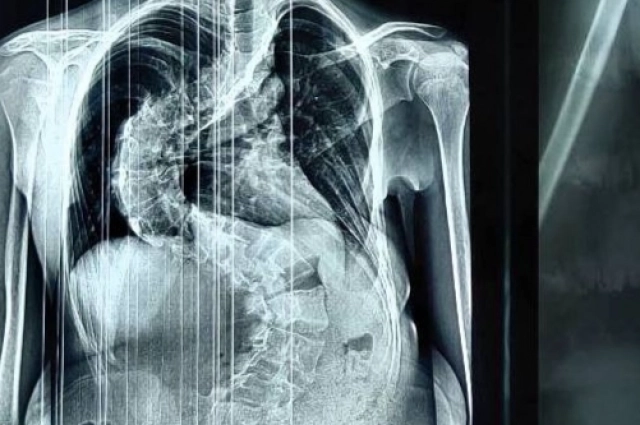

«Сколиоз 4 степени — это серьёзная патология, которая развивается в результате прогрессирования более лёгких стадий болезни, — говорят в минздраве Кировской области. — Деформация позвоночника при таком состоянии становится ярко выраженной и заметной визуально, у больного присутствует сильная асимметрия тела — плеч, зоны лопаток и рёбер, нарушена походка. Единственным эффективным методом лечения на данной стадии является оперативное вмешательство».

Как рассказал заведующий детским травматолого-ортопедическим отделением Алексей Молчанов, пациентке диагностирован диспластический s-образный грудопоясничный сколиоз 4 степени.

«Несмотря на молодой возраст, тяжёлая, ригидная деформация уже сформировалась. Позвоночник девочки был сильно деформирован и по форме напоминал латинскую букву S. При наклоне туловища вперёд в грудном отделе справа определялся пологий рёберный горб, правое надплечье было выше левого на 2 см», — рассказал врач.

По словам Алексея Молчанова, сколиоз такой тяжёлой формы вызывает множество изменений в организме и приводит к необратимым последствиям для дыхательной, сердечной и других важнейших функций организма. Страдают внутренние органы. В том числе жизненно важные.

«Позвоночник девочки был сильно деформирован. Деформация сжала левое лёгкое, сердце сместилось в правую сторону. Сколиоз такой тяжёлой формы мог привести к необратимым последствиям для дыхательной, сердечной и других важнейших функций организма. Оперативное вмешательство было жизненно необходимо», — пояснил Алексей Молчанов.